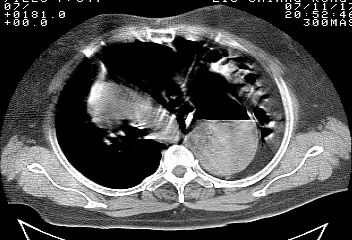

标题: CT10753:女, 64岁 隔疝 [打印本页]

标题: CT10753:女, 64岁 隔疝

女, 64岁 三十年前胸部外伤史, 间断胸闷,

典型左侧膈疝,疝出物为胃和大网膜,纵隔右移

同意左侧膈疝,不过,有过外伤史,左肺有受压征象,同时有胸膜增厚。